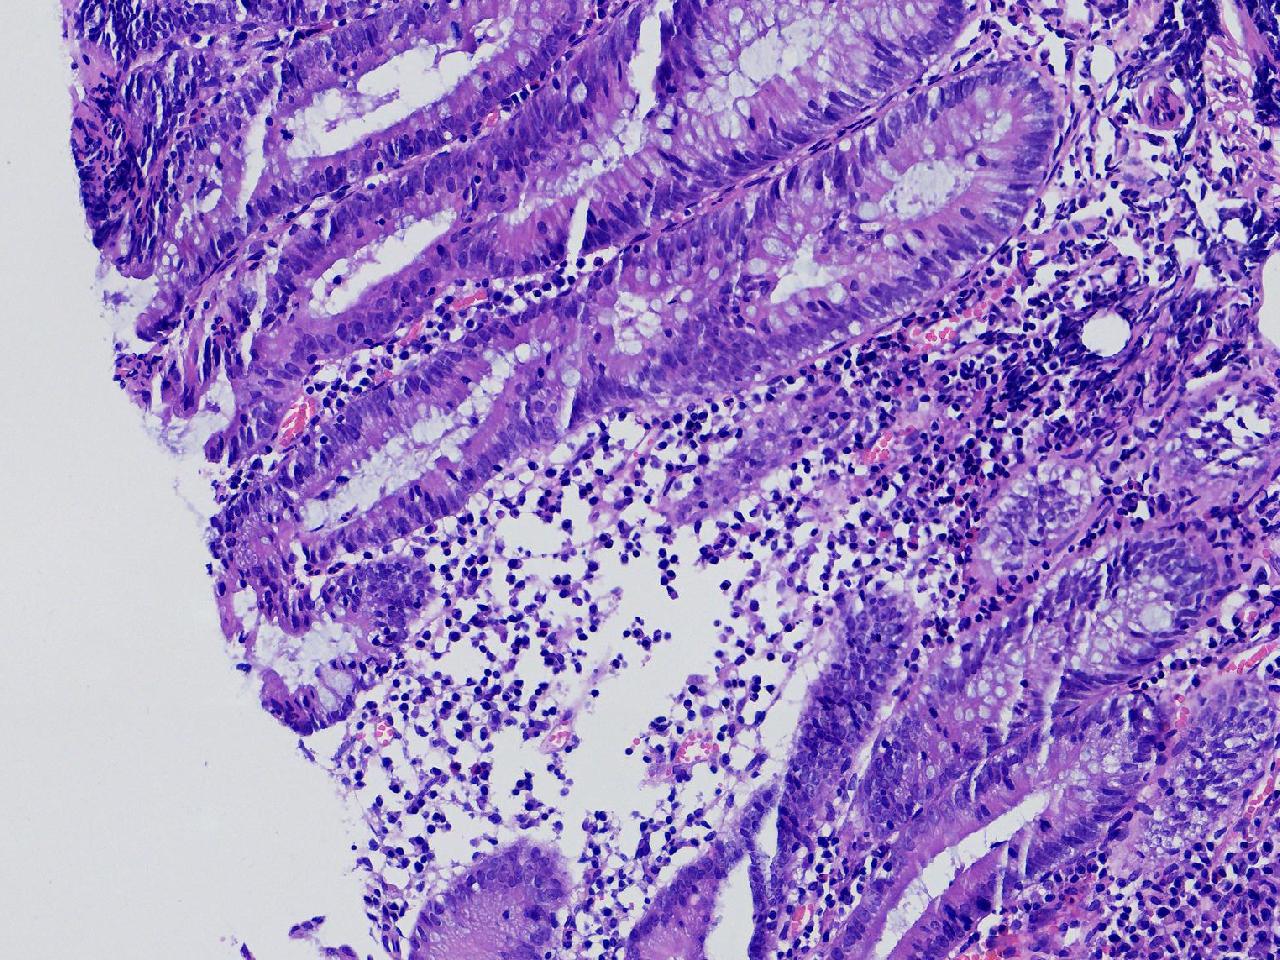

男,62岁,直肠见一直径约0.8cm大小的扁平隆起,表面光滑,活检1块。

直肠活检

灰白色不整形软组织1块,直径0.2厘米。

隐窝脓肿,杯状细胞减少,溃结考虑吗

炎症性肠病,溃结可能

不除外炎症性肠病,结合临床。